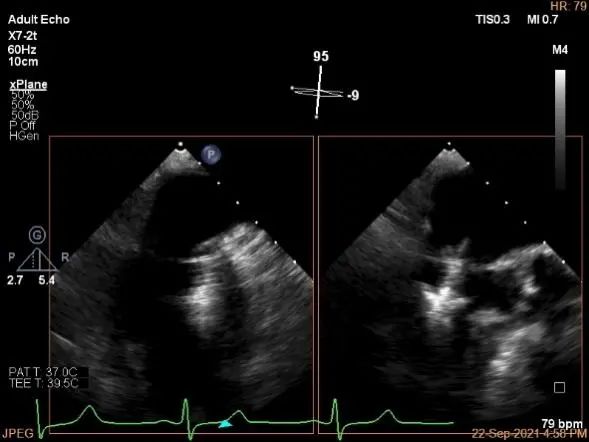

术中超声

3D:P1区脱垂并腱索断裂,Width:11.4mm

3D-color:重度MR,4级

麻醉状态下肺静脉血流频谱

MVA:7.8cm²,平均跨瓣压差:1mmHg

房间隔穿刺点选择

穿刺高度:4.08cm

瓣叶捕获后,计算前叶捕获长度9mm,后叶捕获长度7mm。

夹子夹闭后,未见明确残余分流

3d确认夹子位置在P1区

3d-color确认残余分流情况

评估二尖瓣瓣口平均跨瓣压差:1mmHg

肺静脉血流频谱恢复正常